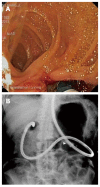

Endoscopic retrograde cholangiopancreatography (ERCP) in patients with surgically altered anatomy is challenging. Several operative interventions of both the gastrointestinal tract and the biliary and/or pancreatic system lead to altered anatomy, rendering ERCP more difficult or even impossible with a conventional side-viewing duodenoscope. Adapted endoscopes are available to reach the biliopancreatic system and to perform ERCP in patients with altered anatomy. However, both technical difficulties and complications determine the procedure's success. Different technical approaches have been described and are highly dependent on local expertise and endoscopic equipment. Standardized practical guidelines are currently unavailable. This review focuses on the challenges encountered during ERCP in patients with altered anatomy and how to deal with them. The first challenge is reaching the papilla or the bilioenteric/pancreatoenteric anastomosis in the patient with postoperative altered anatomy. The second challenge is the cannulation of the biliopancreatic system and performing all conventional ERCP interventions and the third challenge is the control of possible complications. The available literature data on this topic is reviewed and illustrated with clinical cases.